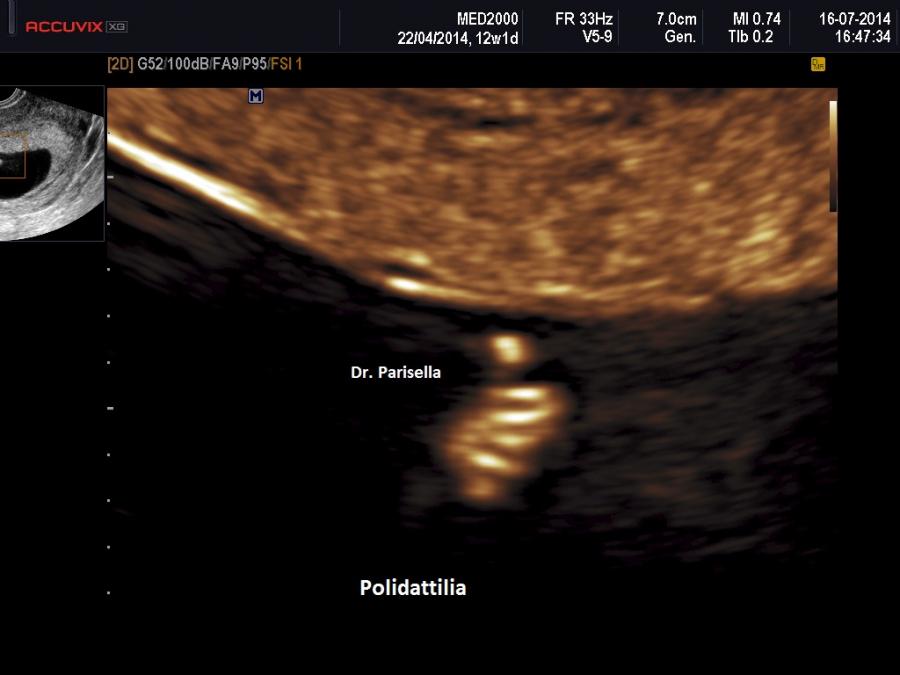

Le anomalie scheletriche sono sindattilia che interessa caratteristicamente il II-III dito dei piedi, polidattilia postassiale, rizomelia, pollici corti.